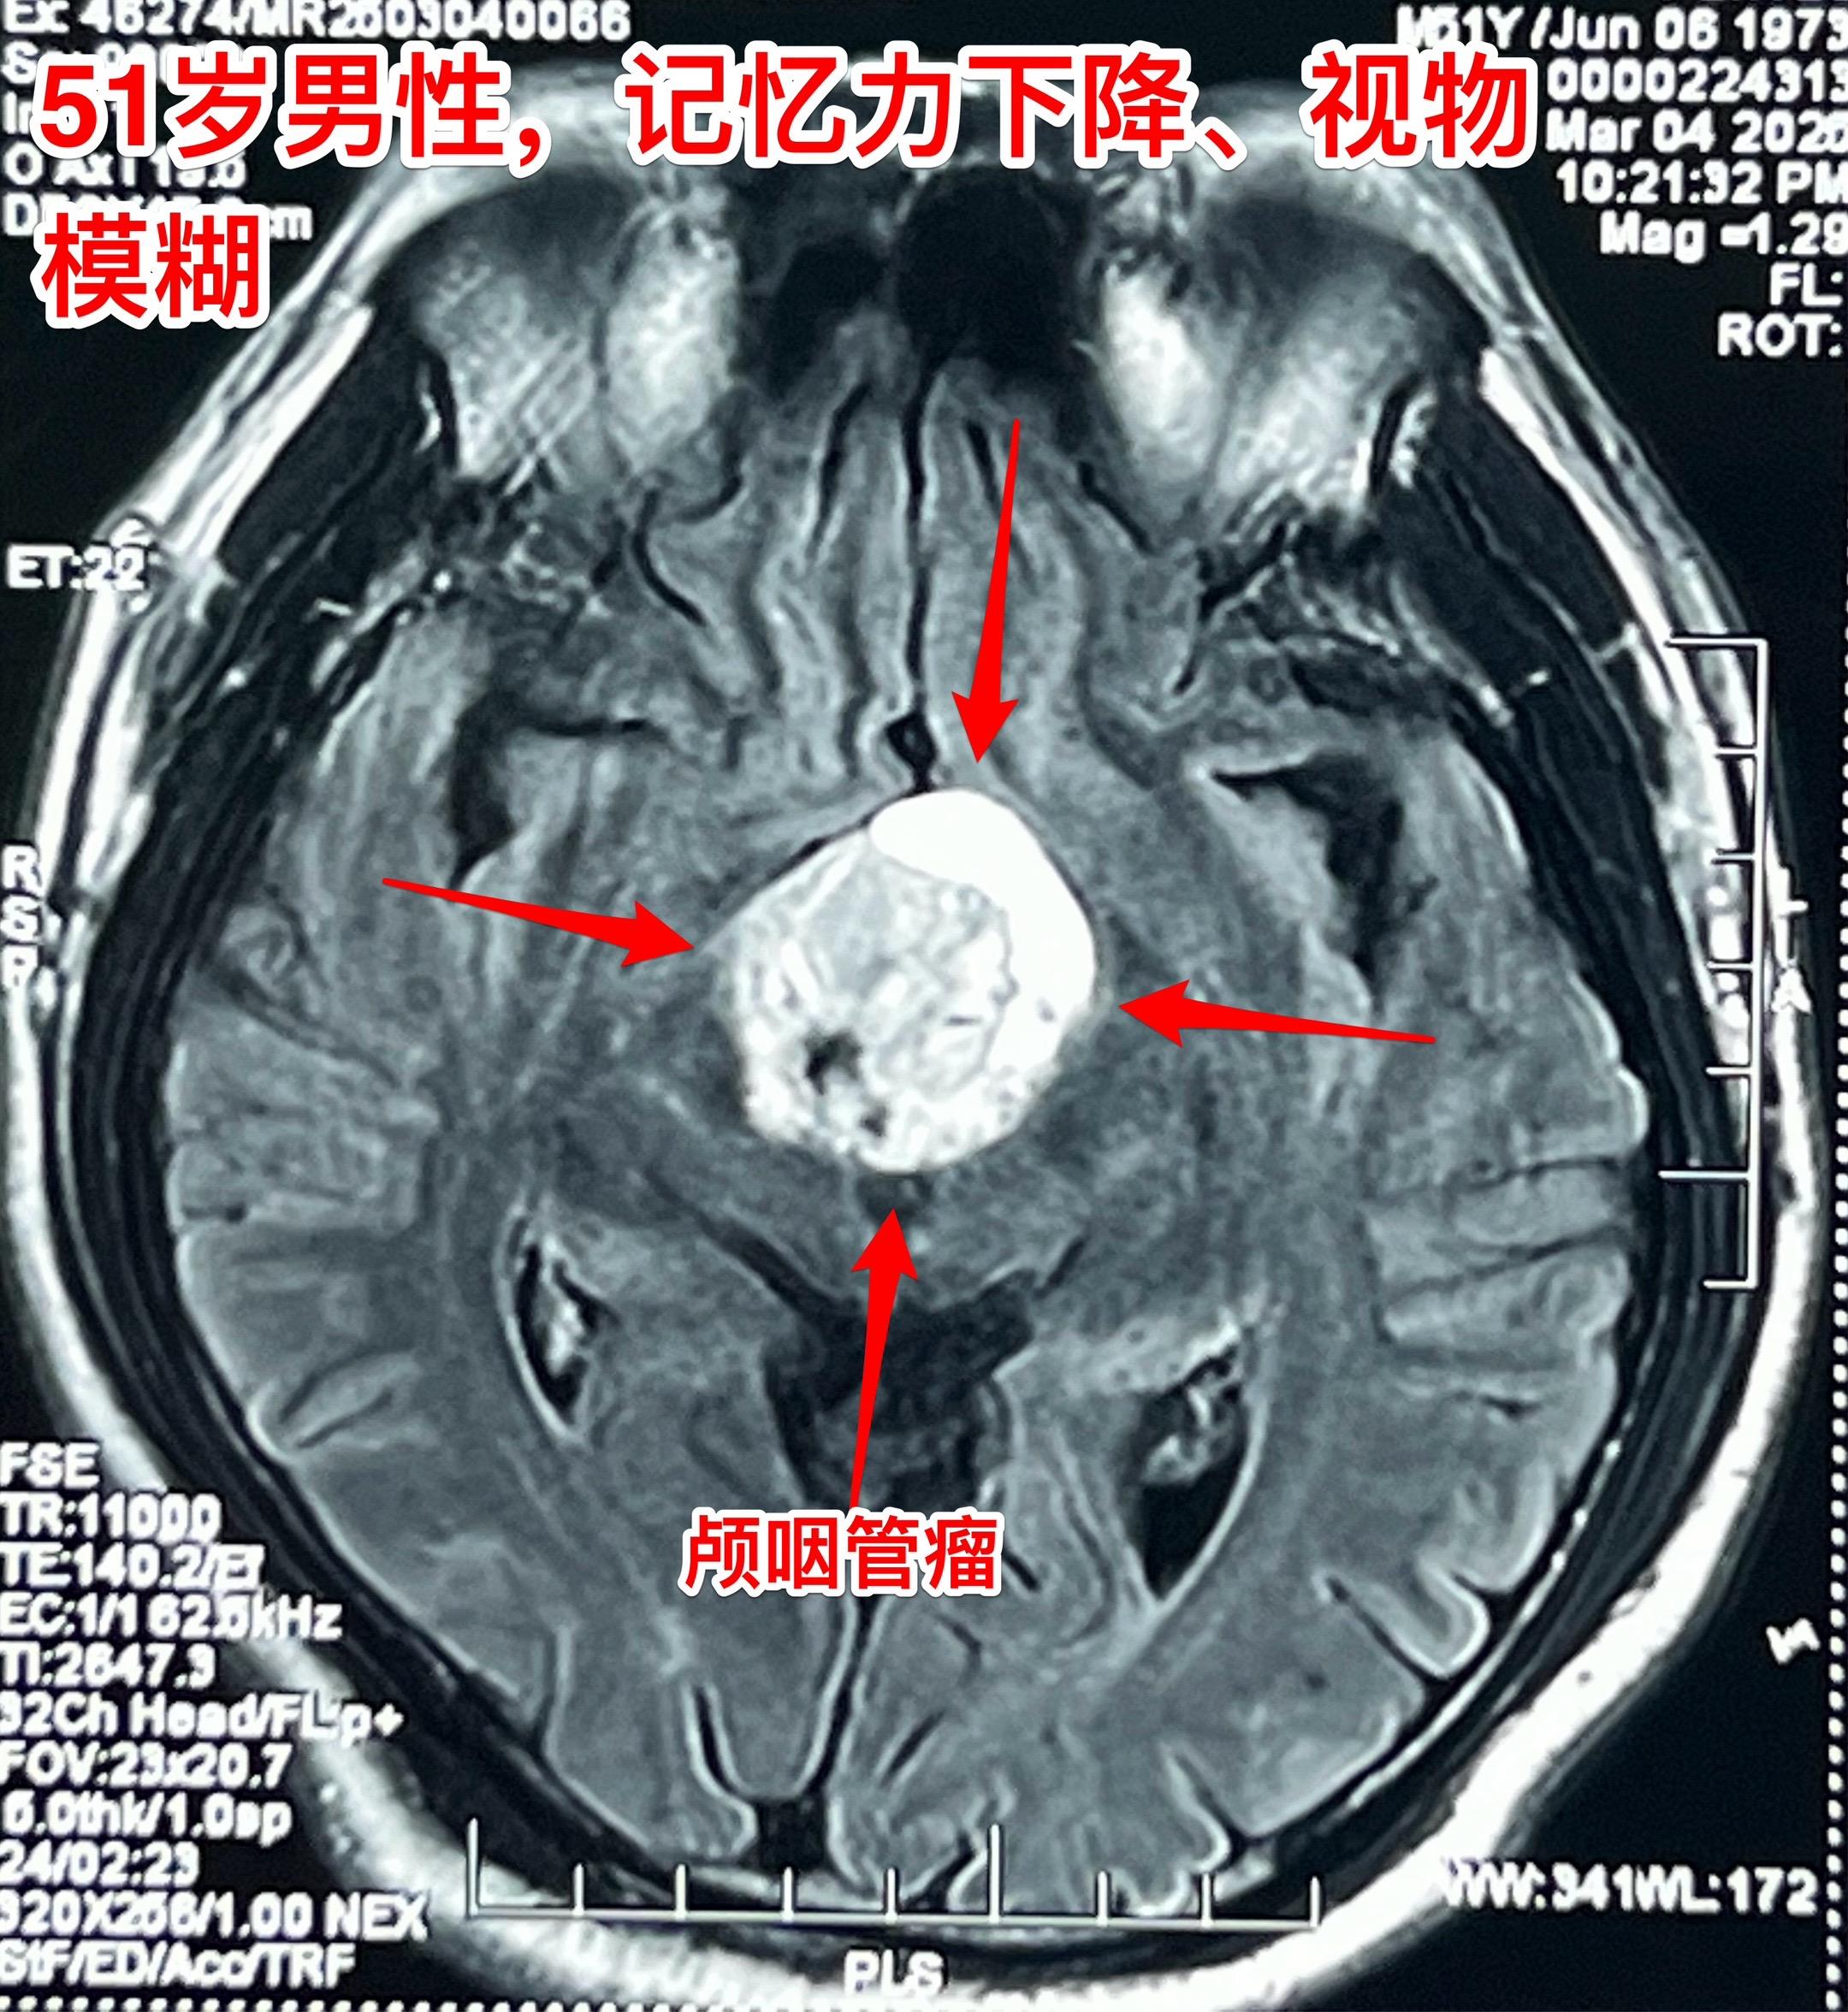

昨日一个颅咽管瘤手术+一个胶质瘤手术。昨日第一个手术:51岁男性,卡车司机,因记忆力下降、视物模糊检查发现颅咽管瘤,见图。肿瘤主体位于第三脑室内,实性肿瘤,有小块钙化斑。术中见肿瘤呈肉乎乎的,有细小钙化斑。肿瘤完全切除,垂体柄保留约40%。术后CT未见术区出血。 第2个病人是大同市女性,39岁,因头痛、呕吐到医院检查发现左侧脑部肿瘤,考虑为高级别胶质瘤。这个胶质瘤内血管粗大、扩张 怀疑有动脉瘤,是个血供十分丰富的肿瘤。术中看见肿瘤内血管粗大,像动脉瘤一样扩张,肿瘤呈暗红色,质地较韧,血供丰富